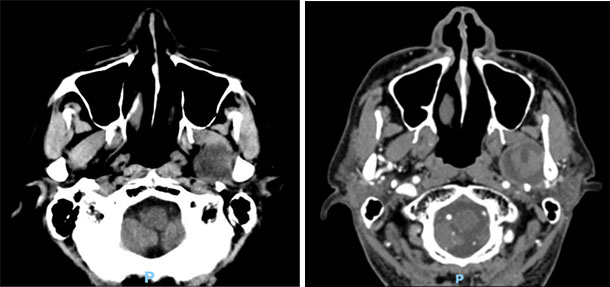

接受手术的是一名65岁男性患者,因“走路时偶有头晕”到某医院就诊,头颅CT检查结果示:左侧咽旁颅底占位性病变。得知病严重,遂来我院求治。入院完善相关检验检查后,科室主任朱李军主任主持口腔颌面外科专家对拟行手术方案予以充分的论证。肿瘤占位于左侧侧颅底肿物位于翼外肌肉深面,与颈内静脉、面神经总干解剖毗邻,肿物位置深在。口腔颌面外科计划口前-下颌颈入路,于下颌骨体部截断下颌骨,截断其周围肌肉附丽以显露肿物。

术前CT检查